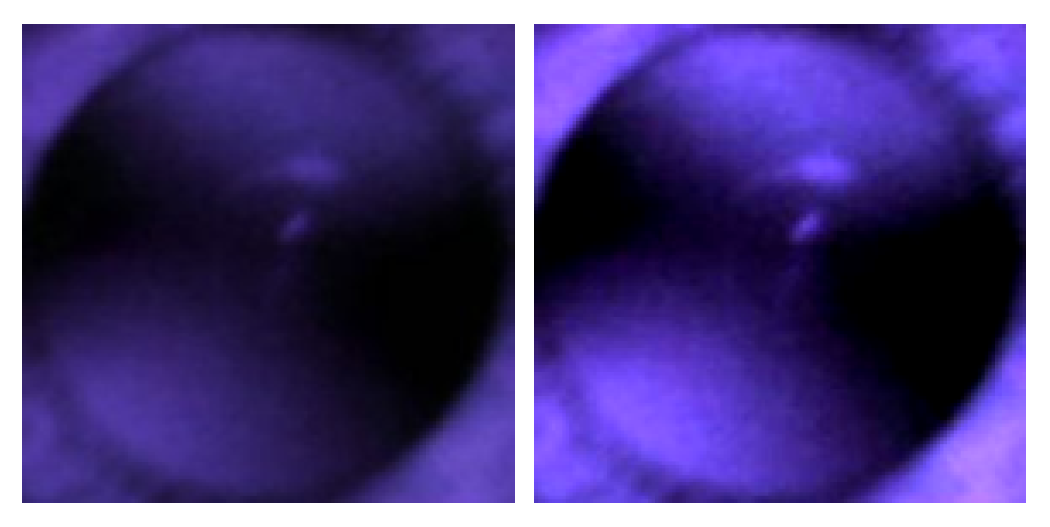

2.2. IR-Based Imaging with nun IR

2.3. Observation of Crescents

3.4. Increasing Contrast